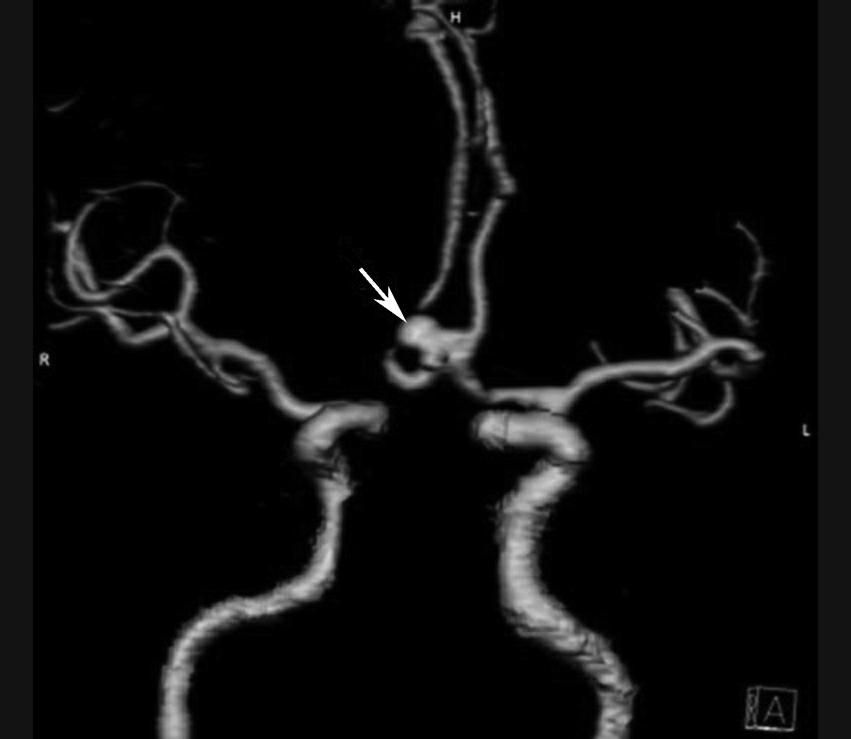

基底动脉开窗畸形的发生机制被认为是胚胎第5周时成对的胚胎性神经动脉融合障碍,或为原始侧动脉残留所致(图1-2-78)。

图1-2-78 基底动脉开窗畸形(箭)